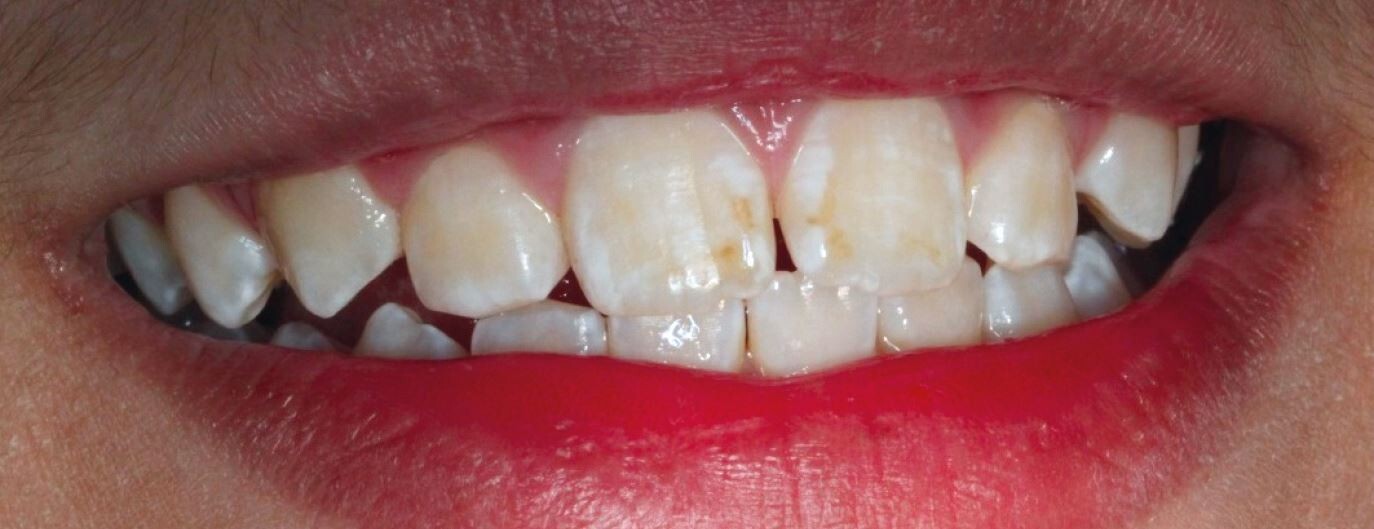

Enamel hypomineralisation happens when the mineralisation process is not fully achieved, resulting in discoloured enamel. This condition also weakens the teeth, which means that teeth can break down. The Australian Academy of Pediatric Dentistry also explains that hypomineralisation is prevalent in a fifth of all children. It can appear as discoloured patches of soft or decaying, bumpy enamel that usually affect the molars and incisors as they grow in. Teeth with hypomineralisation are sensitive and can cause children pain when eating; these teeth typically start to deteriorate once they grow in.

On the other hand, enamel hypoplasia is a condition where teeth have pits, grooves, and missing enamel. It can also result in smaller teeth. Hypoplasia appears as brown or yellow stains and exposed dentin. While the enamel is still hard, it is weak. This is a type of amelogenesis imperfecta, where the enamel on teeth is missing or severely thin and prone to breaking.